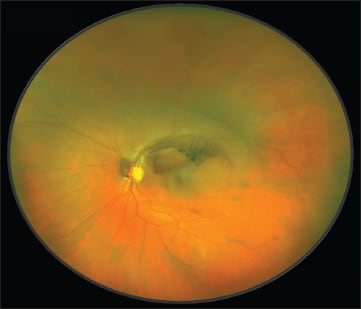

Next was the case of a 16-year-old girl who presented with a scotoma and CNV, as well as yellowish lesions along the superotemporal arcade (Figure 9). FA showed active neovascularization which was seen better with indocyanine green angiography (Figure 10). With OCT, a diagnosis of multifocal choroiditis (Figure 11) with its inflammatory type of CNV was made.

Figure 9. This 16-year-old girl had a scotoma and CNV, as well as yellowish lesions along the superotemporal arcade.